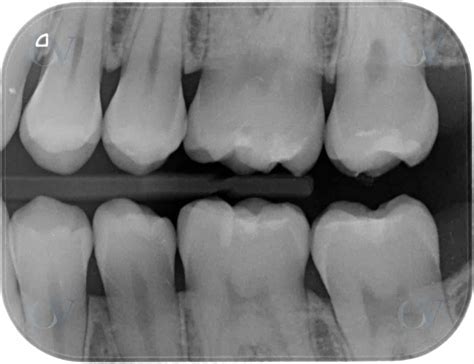

Radiografías de Aleta de Mordida

El diagnóstico de caries interproximales en el esmalte se realiza mejor mediante radiografías de aleta de mordida, que son el mejor factor predictor de una futura lesión en dentina. En casos de lesiones en la superficie interproximal, el método radiográfico es útil, aunque tiene limitaciones en la detección de lesiones incipientes en comparación con los métodos visuales, táctiles y de fluorescencia.

Radiografía de aleta de mordida para detectar caries interproximales.